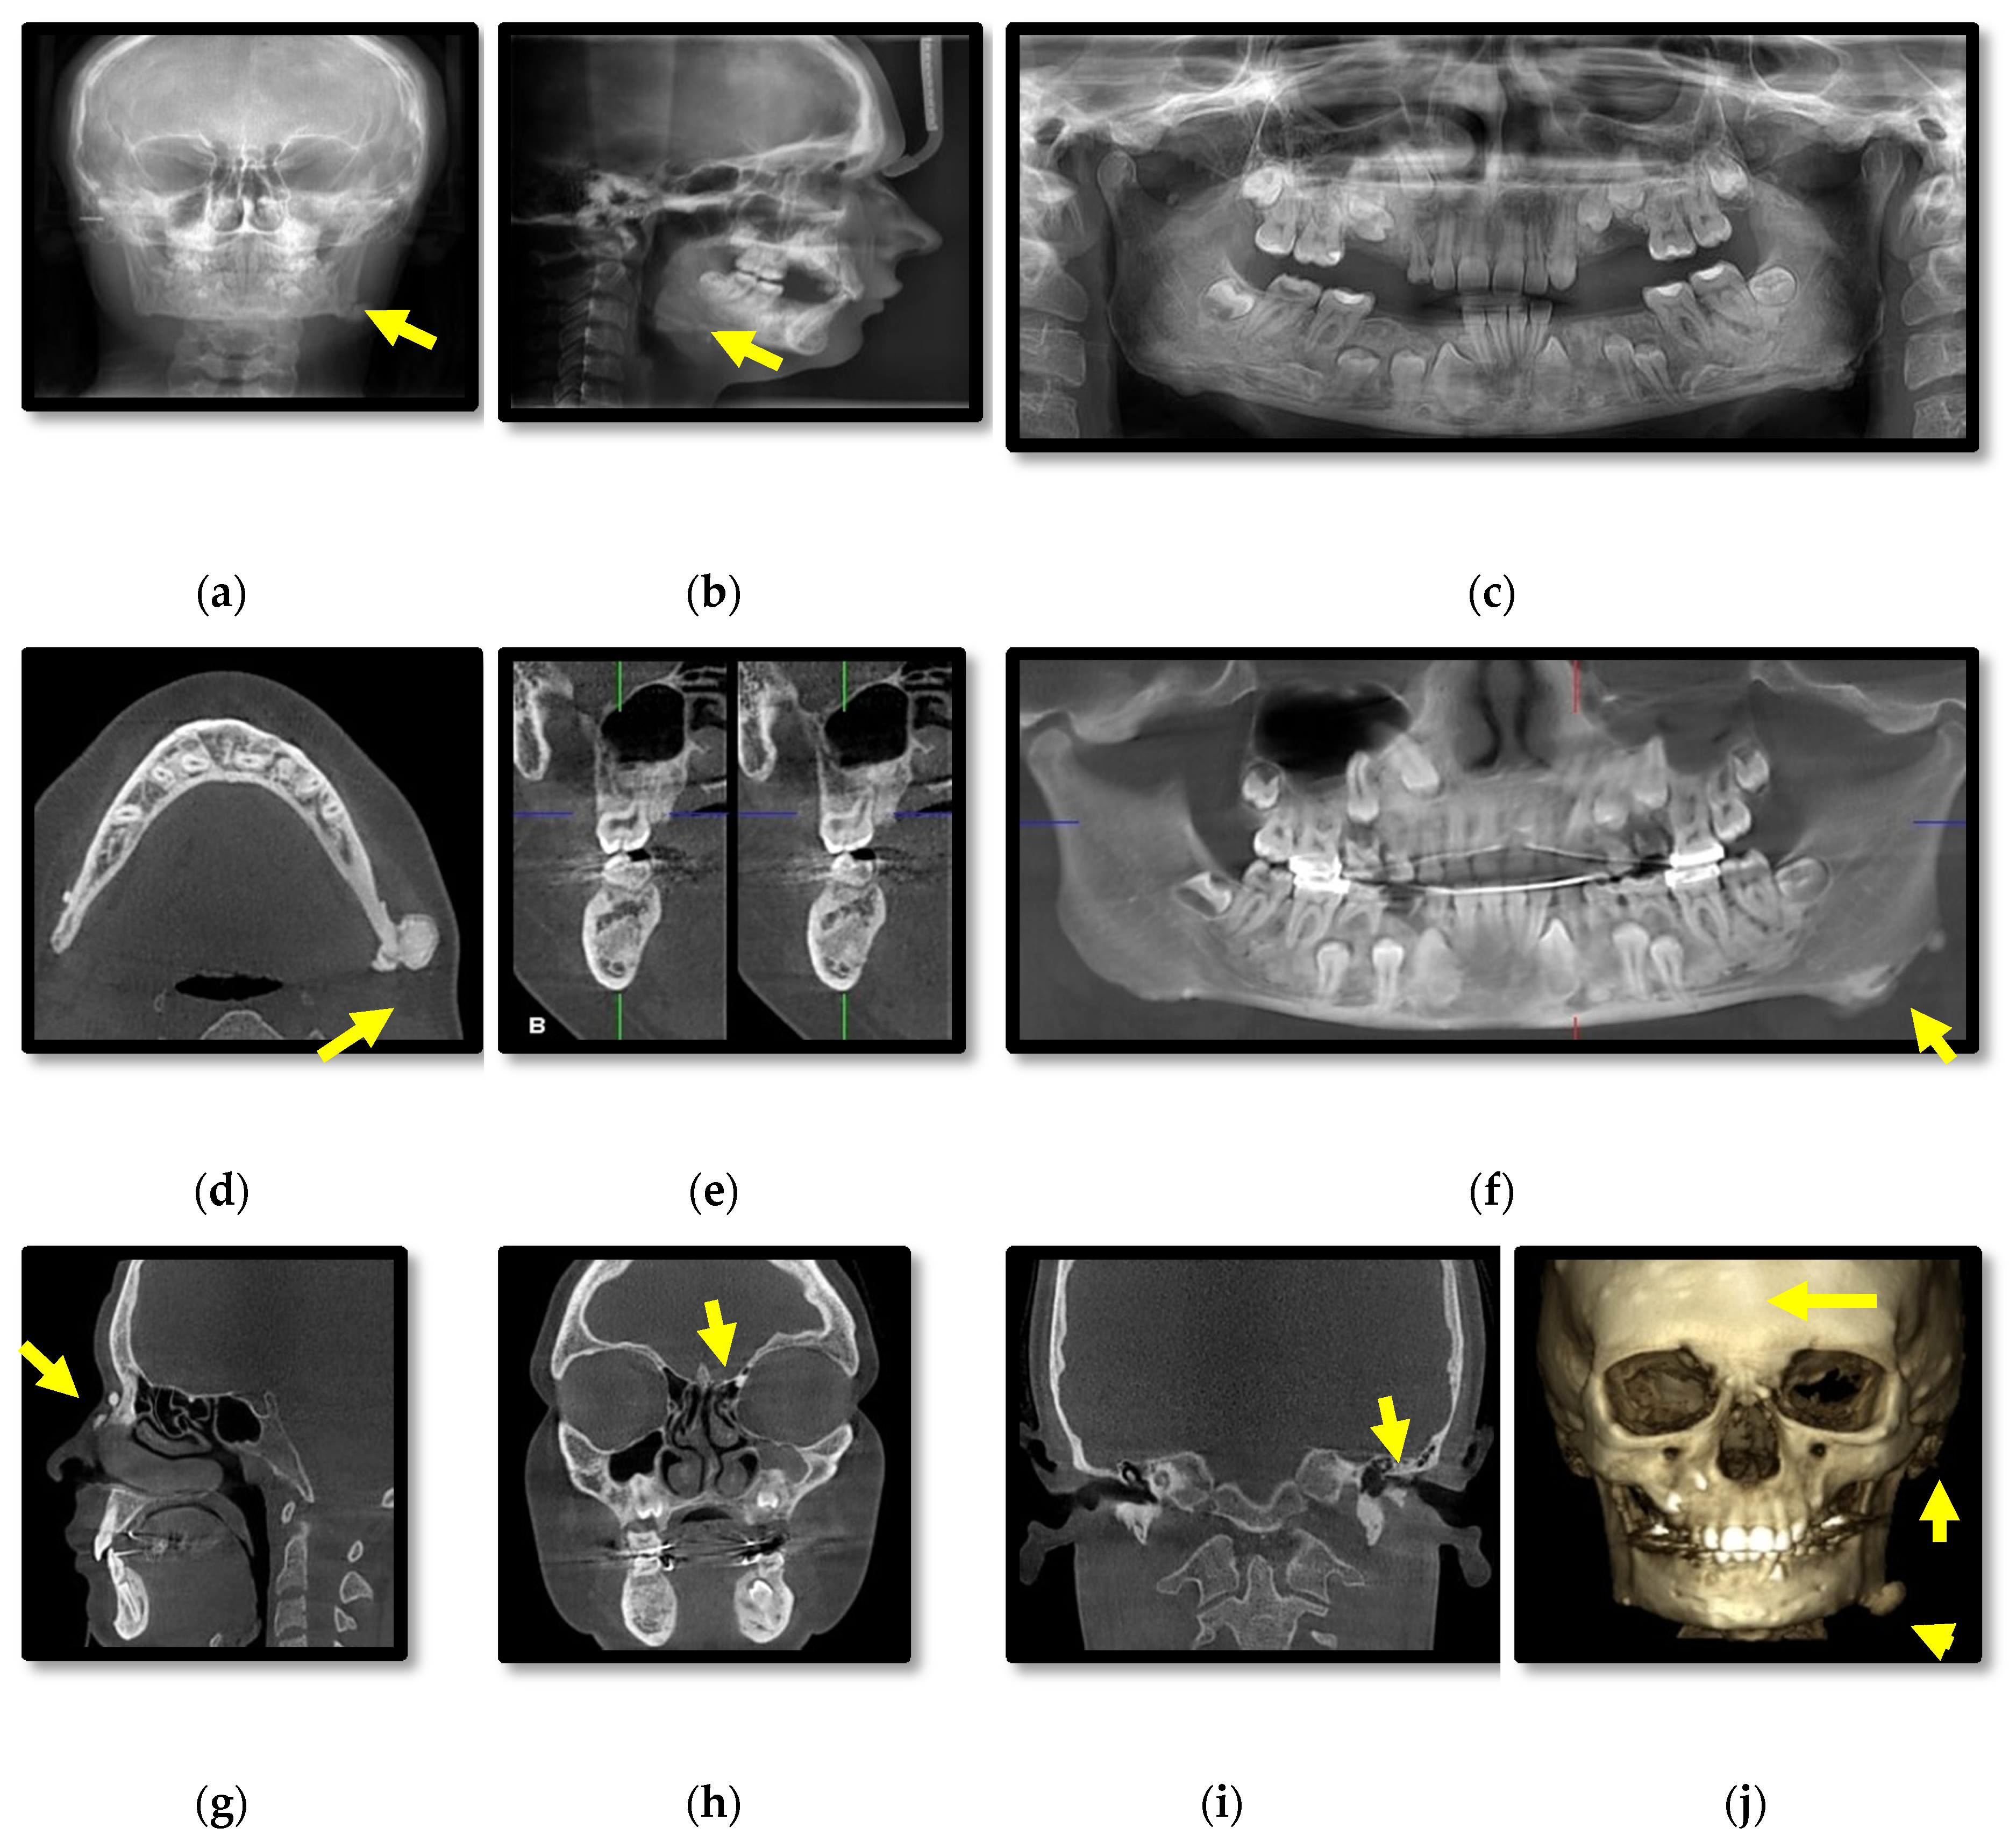

3.1. Radiographic Assessment

4.2. Osteomas

- Cankaya, A.B.; Erdem, M.A.; Isler, S.C.; Cifter, M.; Olgac, V.; Kasapoglu, C.; Oral, C.K. Oral and maxillofacial considerations in Gardner’s syndrome. Int. J. Med. Sci. 2012, 9, 137. [Google Scholar] [CrossRef] [PubMed]

- Almeida, F.T.; Pachêco-Pereira, C.; Porporatti, A.L.; Flores-Mir, C.; Leite, A.F.; De Luca Canto, G.; Guerra, E.N.S. Oral manifestations in patients with familial adenomatous polyposis: A systematic review and meta-analysis. J. Gastroenterol. Hepatol. 2016, 31, 527–540. [Google Scholar] [CrossRef] [PubMed]

- Wijn, M.A.; Keller, J.J.; Giardiello, F.M.; Brand, H.S. Oral and maxillofacial manifestations of familial adenomatous polyposis. Oral Dis. 2007, 13, 360–365. [Google Scholar] [CrossRef] [PubMed]